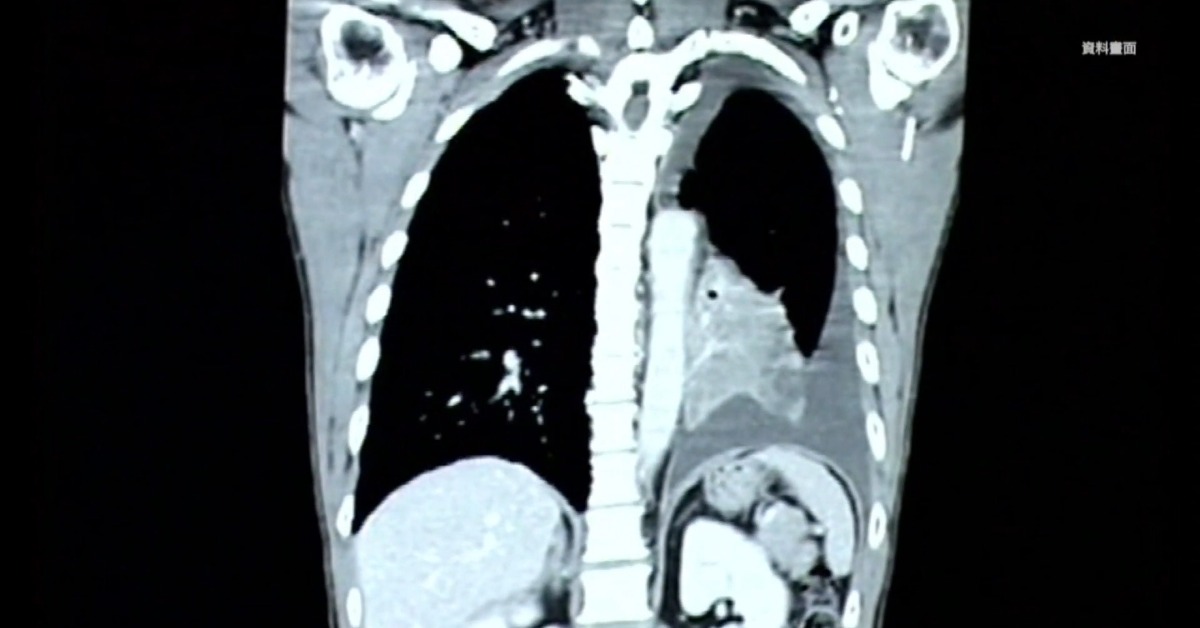

肺癌不只連44年穩居癌症死因前2名,更是十大癌症中最花錢的「國病」。(圖/東森新聞)

肺癌奪命也燒錢!根據衛福部最新統計,肺癌不只連44年穩居癌症死因前二名,更是十大癌症中最花錢的「國病」,從健保支出到自費藥物,樣樣驚人,醫師更直言,空氣污染問題不解決,肺癌災難恐怕只會越演越烈。